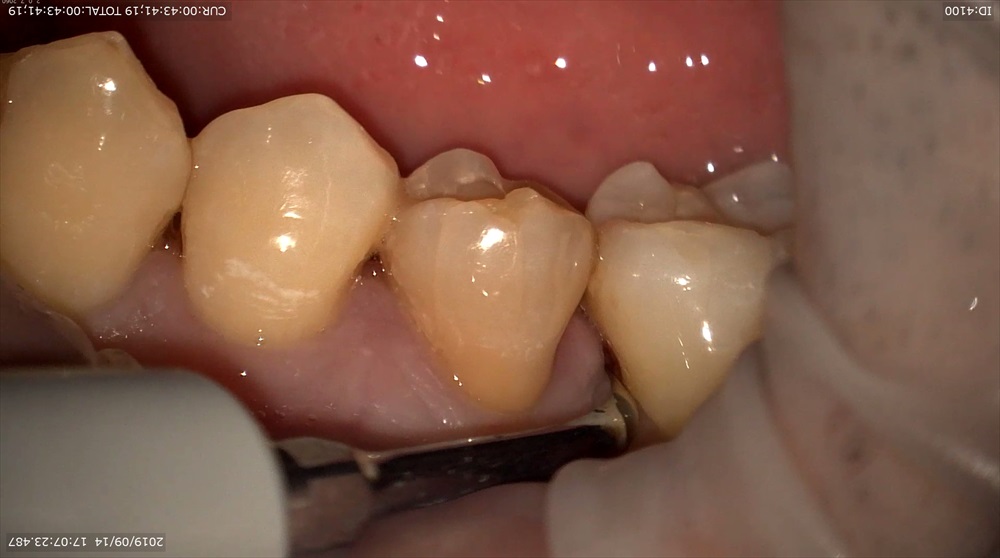

そして、20倍!!

3倍率では分かりにくかった黒点がこんなにも傷ついているのが分かると思います。

歯石が歯周ポケット内に付いているのがお分かりいただけるでしょうか?

しっかり取り除けたながわかると思います!